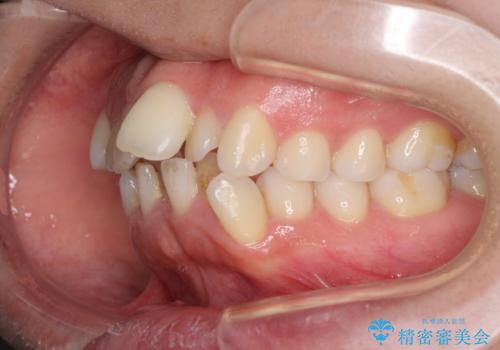

- 前歯のデコボコと口元の突出感を気にして来院された患者様です。

上下左右第一小臼歯4本を抜歯し、ワイヤー装置にて口元を引っ込めるよう矯正治療を行うこととしました。

叢生が強かったため、口元の突出感の改善には限界がありましたが、横側からも口元が引っ込んだ感じが分かるほど改善されました。